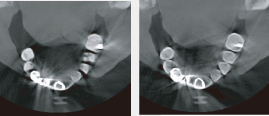

サンプル映像イメージ